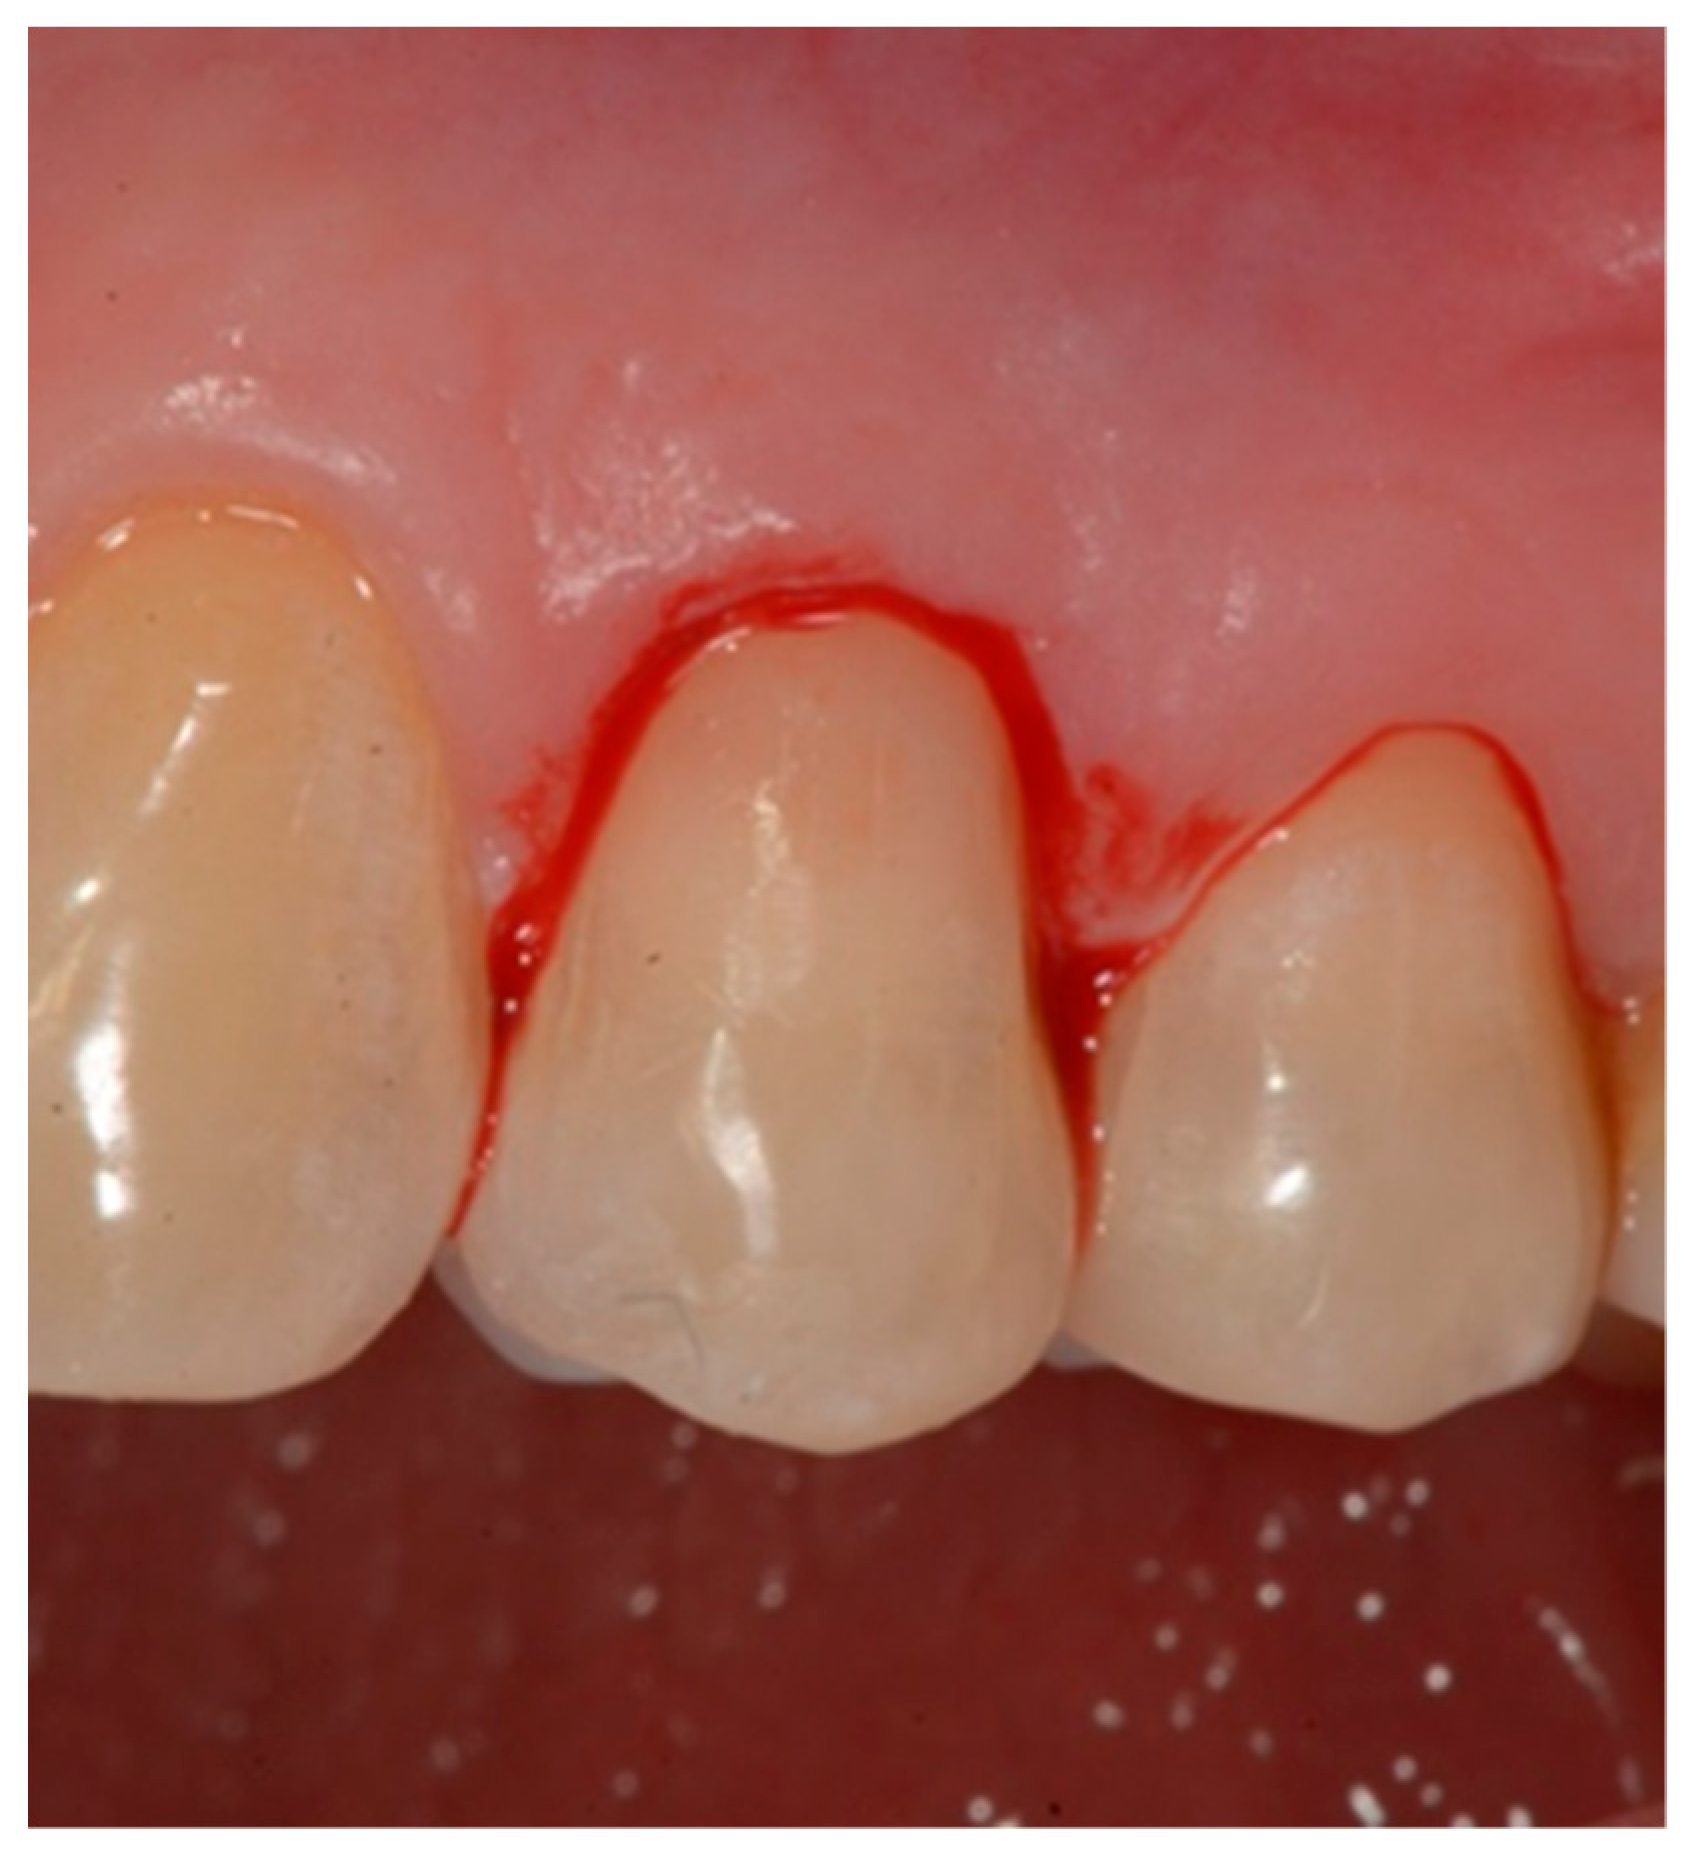

- Initial measurement of the length of the clinical dental crown (performed with a millimeter periodontal probe placed adjacent to the dental crown and having as a reference the most apical part of the gingival sulcus and the highest part of the crown) and photography of the lesions at time 0 (t0) (Figure 2a).